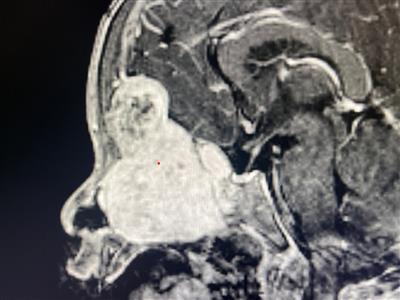

A 2-year-old child from Sonipat, Haryana, presented with worsening complaints of protrusion of the left eyeball, fixity of eye movements, snoring, a mass seen via the left nostril, and excessive watering of the eye. CT/MRI showed a 7 cm giant anterior skull base tumor involving the nose, sinuses, brain, and orbit. The biopsy turned out to be a meningioma. It is extremely rare in children, and the only other similar case reported previously in 2020 was in a 12-year-old girl from Spain who also needed open surgery.

As the tumor was extending down through the nose and laterally involving the maxillary sinus and orbit, the child needed expanded endonasal endoscopy with the creation of additional space by nibbling the anterior cheekbone. Navigation, 45-degree angled endoscope, coblator, and long curved instruments were used innovatively to reach the upper part of the tumor adjacent to the brain. The tumor was very vascular, involving multiple bones and crevices. As the tumor was meticulously removed entirely with just endoscopy via the nose, the open neurosurgery was not required. The huge defect in the skull base created by the tumor was repaired in multiple layers. The preparation and procedure as a whole lasted 9 hours. The patient has improved after surgery. MRI has confirmed total excision.